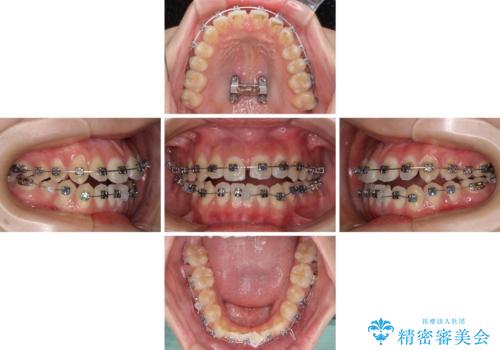

受け口と開咬を急速拡大装置とワイヤー装置で改善

- メタルブラケット

- 前歯の開咬と、受け口による咬み合わせの悪さを気にして来院された患者様です。

上顎歯列が狭窄していたため、急速拡大装置により上顎骨を側方に拡大し、その後ワイヤー装置にて矯正治療を行うこととしました。

舌の突出癖が開咬の原因であったので、改善のための舌トレーニングを行っていただきました。

舌トレーニングは後戻りにも大きく影響するため、とても重要なトレーニングです。